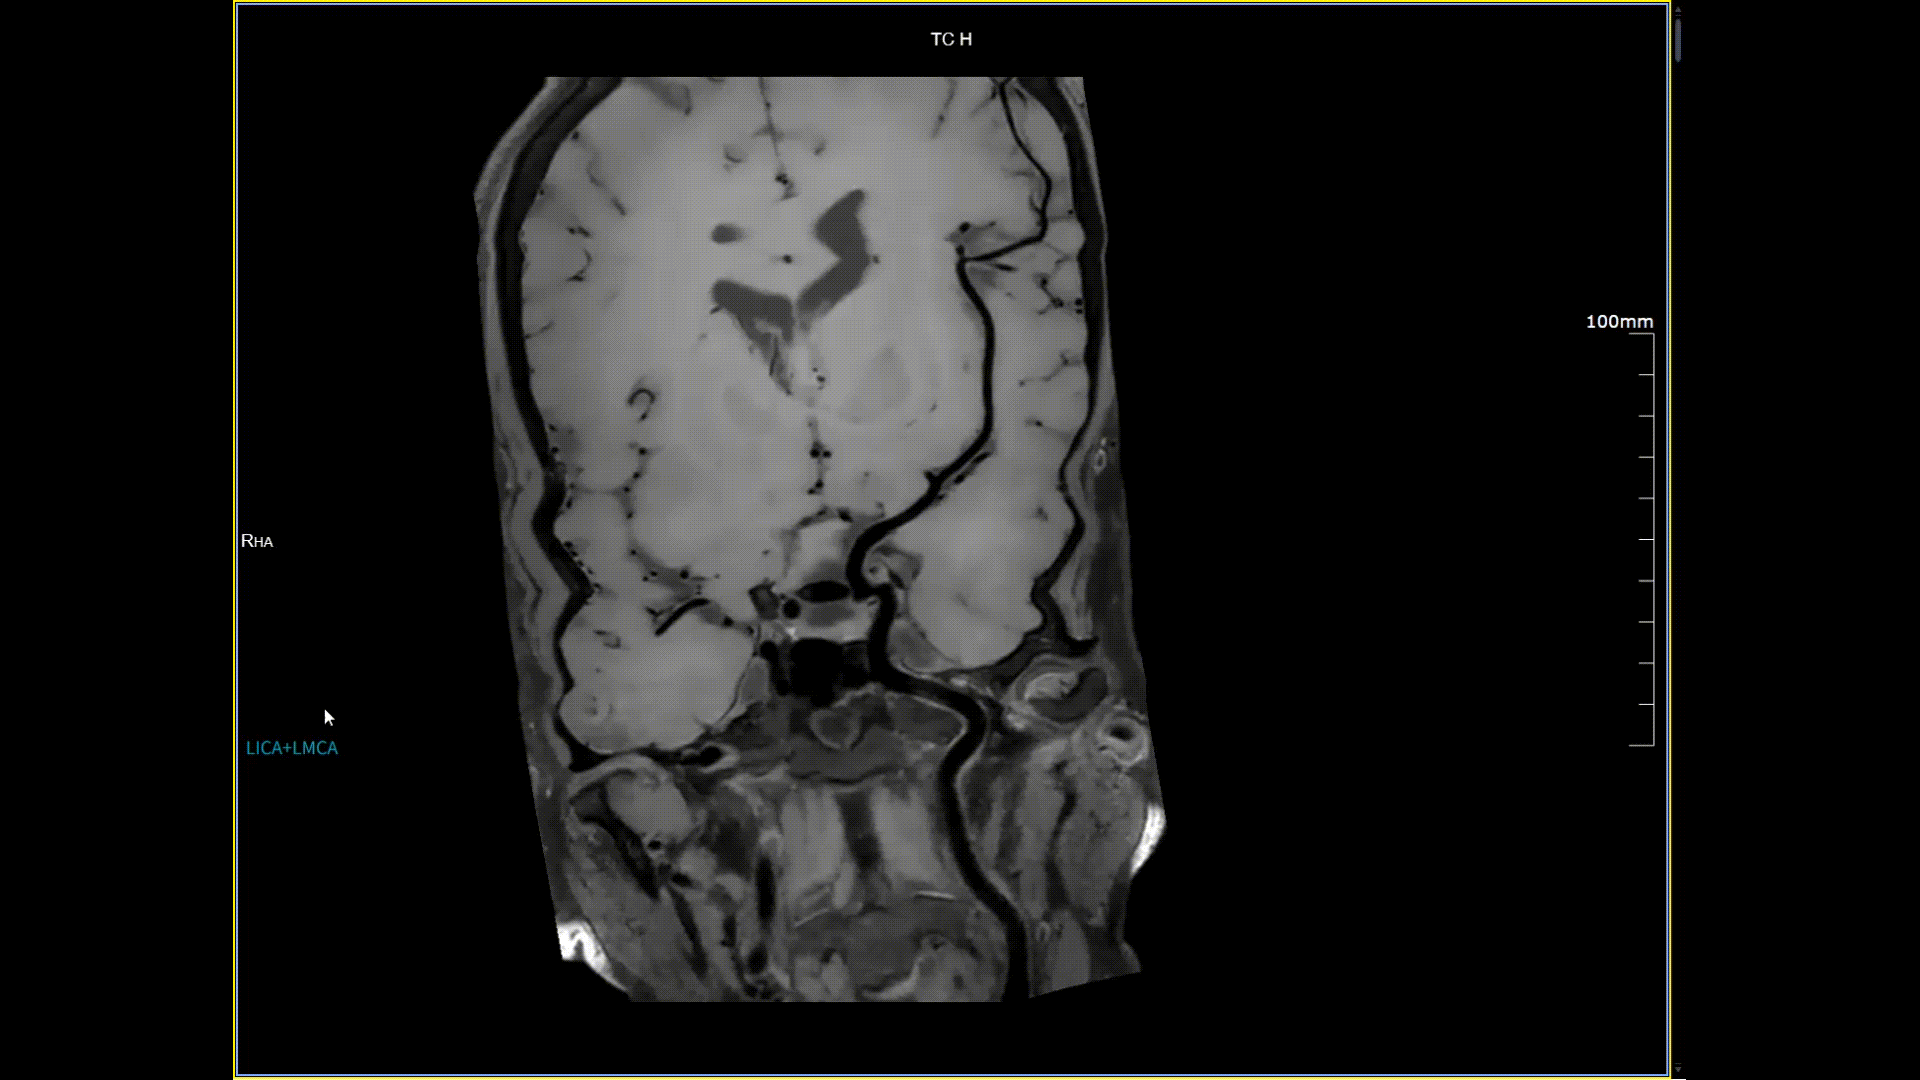

头颈血管斑块,分辨率0.4*0.4mm

5.0T磁场强度远高于其他设备,使得氢原子核在磁场中的响应信号极大地增强。这就像在安静的房间里能听清细微的声音一样,高信噪比能让医生看到更微小、更模糊的病变结构。例如上述患者的检查,该设备可以呈现0.2x0.2毫米高分辨率的图像以及动态显示血管走行,使得病变血管的细微解剖结构、分布及其与周边脑组织的关系得以直观呈现,为临床医生进行精准诊断并制定后续治疗方案提供了重要的影像学依据。